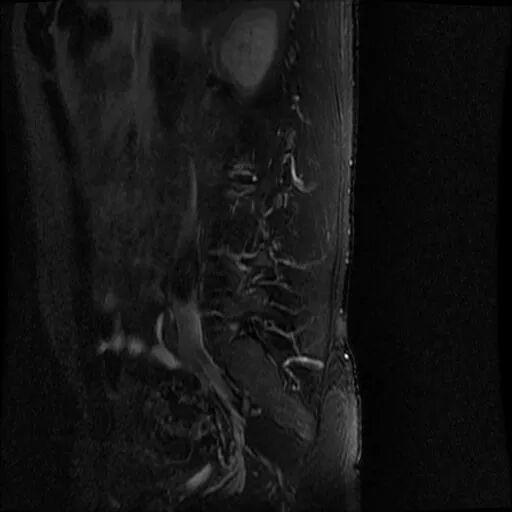

術(shù)前影像資料

圖1:術(shù)前MRI

?

圖2:術(shù)前MRI